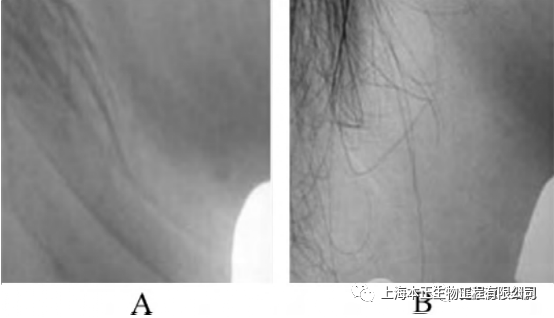

本研究表明,将间充质干细胞应用于整形外科治疗之中可以获得理想的效果,是一种安全、有效的治疗方案,值得临床推广使用。患者,女,37 岁,颈部皱纹过多自愿要求接受干细胞治疗,治疗后未出现感染等,随访12个月,颈部皱纹明显减少,患者对治疗效果表示满意。

A: 治疗前, 存在明显的颈部皱纹;

B: 治疗后12个月, 皱纹明显减少